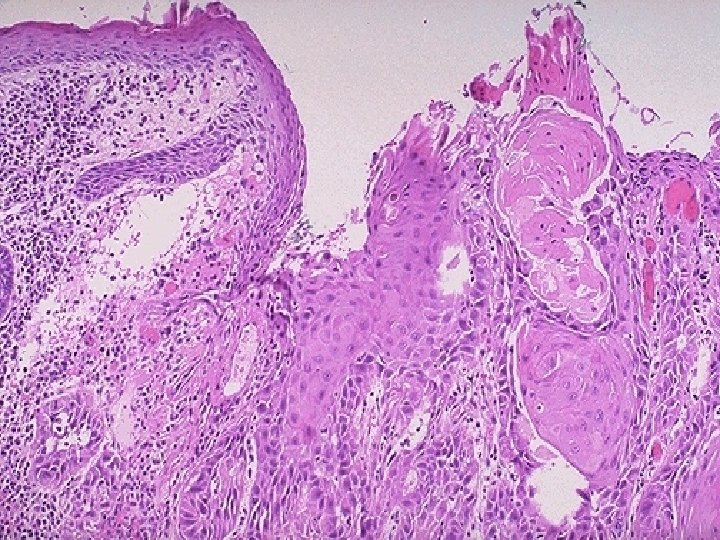

Nasopharyngeal Carcinoma: Most important etiology is EBV with genetic susceptibility. Age: more than 50 years. Three histological subtypes: 1. Keratinizing squamous cell carcinoma. 2. Non keratinizing squamous cell carcinoma. 3. Undifferentiated carcinoma (commonest), which characterized by syncytial growth pattern. The nuclei of nasopharyngeal carcinoma tend to be vesicular, with a smooth outline and a single, large, sharply etched eosinophilic nucleolus.